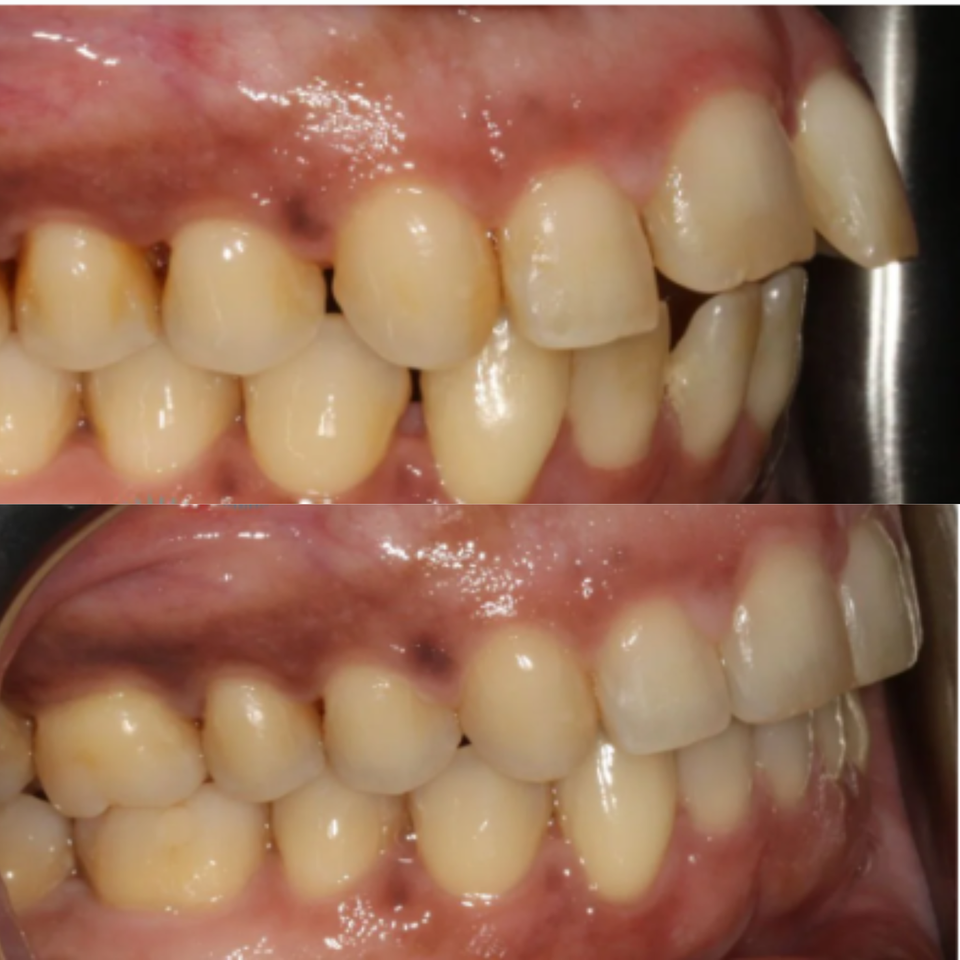

This patient presented with significant gum recession affecting the right central tooth, which ultimately required extraction.

Our team carefully planned and executed the placement of an implant supported crown to achieve a natural looking, fully functional esthetic result. The final outcome not only restored the patient’s smile, but also renewed their confidence.